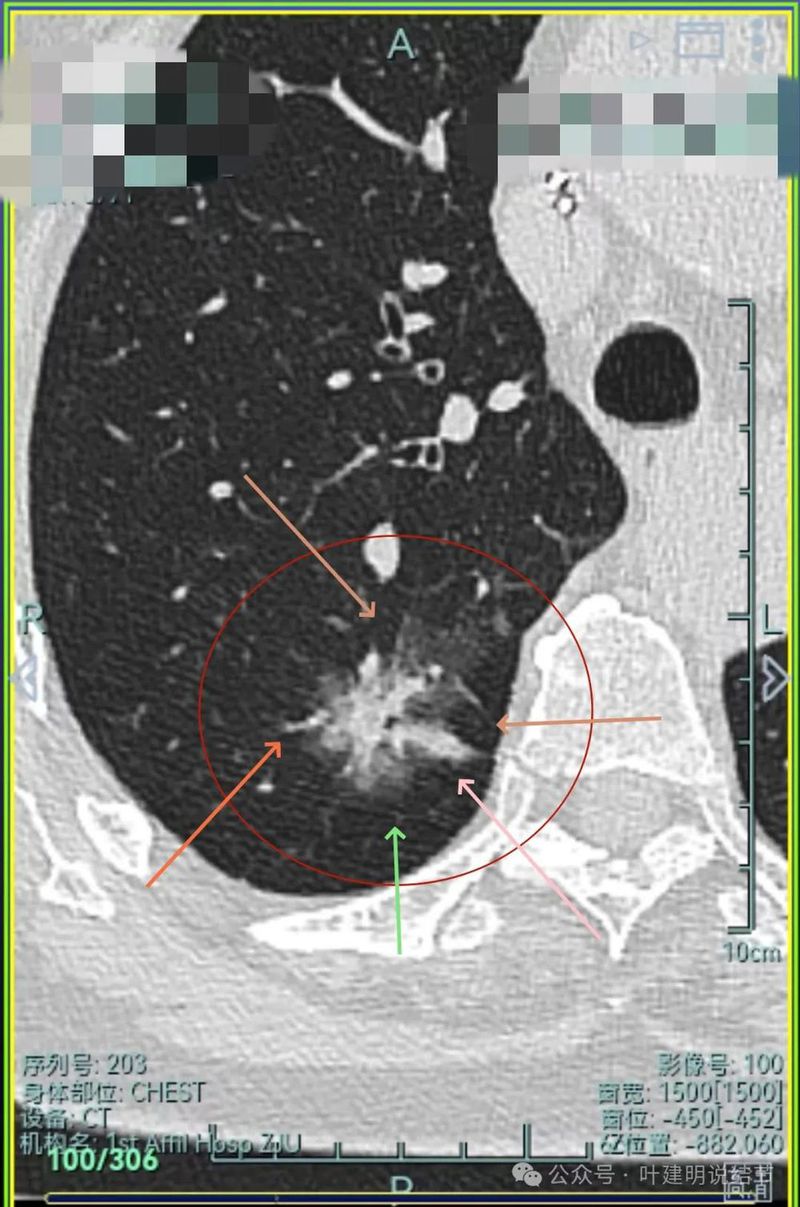

主病灶连续层面展示分析:

病灶出现,磨玻璃密度,轮廓与边界均清楚,灶内密度稍不均。

有明显血管进入,表面分叶,边缘不平,整体轮廓清。

边缘毛刺、表面不平、灶内偏实性成分、分叶明显,整体轮廓与瘤肺边界较为清楚。

灶内细支气管扩张、边缘毛刺较为锐利、有明显磨玻璃成分,磨玻璃成分的瘤肺边界清楚,病灶分叶明显。

灶内密度杂乱不均,内有小空泡征,表面不平。

灶内血管增粗穿行、磨玻璃成分明显,轮廓较清。

血管进入,磨玻璃成分,支气管扩张,边缘不平。

典型混合密度病灶,中间部分密度高偏实性,外围部分磨玻璃密度,两者之间交错存在,说明偏实性部分有侵袭性。磨玻璃成分与正常肺组织之间界限清楚,表面分叶,部分边缘毛刺,整体轮廓清。是非常符合恶性的影像表现。

灶内磨玻璃成分明显,并有异常增粗血管僵硬穿行于病灶内,支气管有扩张通气征,瘤肺边界清楚,实性成分明显。